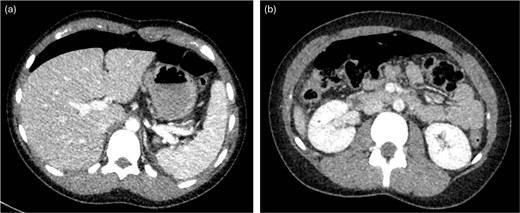

A previously healthy 16-year-old female presented to the emergency department with acute severe abdominal pain, fever, nausea, and vomiting. She was tachycardic and febrile. Abdominal examination revealed diffuse tenderness and mild distension. An upright abdominal X-ray demonstrated pneumoperitoneum. A computed tomography (CT) scan of the abdomen and pelvis (Fig. 1) with intravenous contrast confirmed moderate free-air tracking from the liver to the bladder. Punctate air was also noted along the falciform ligament, overlying the right kidney, and near the left splenic-flexure, accompanied by mild perisplenic and perihepatic free fluid. Multiple air foci within the gastric body and antrum suggested gastric or duodenal ulcers. The patient had recently taken antibiotics for sinusitis and ibuprofen. She underwent immediate diagnostic laparoscopy.

CT with intravenous contrast demonstrating large pneumoperitoneum.